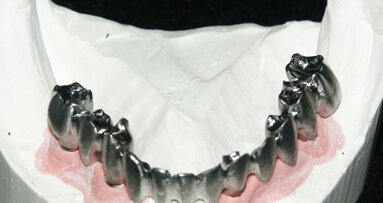

Una paziente di 62 anni, ASA 1 si rivolge alla nostra attenzione per richiedere una riabilitazione dell’arcata mascellare superiore essendo portatrice di protesi mobile totale. L’esame radiologico iniziale evidenzia una marcata atrofia ossea quindi viene progettato l’inserimento di 8 impianti dopo elevazione bilaterale dei seni mascellari al fine di realizzare un a protesi tipo Toronto-Bridge. Trascorsi 8 mesi dai sinus lift e dopo aver accertato la totale guarigione dei siti innestati con una CBCT viene eseguito l’intervento implantare in anestesia locale, sotto profilassi antibiotica, con chiusura dei lembi per prima intenzione e senza eseguire procedure di carico immediato. La paziente viene quindi controllata regolarmente ed a distanza di 7 giorni manifesta una sintomatologia algica localizzata alla zona 1.1 che inizialmente appariva compatibile con il normale decorso post-operatorio. Successivamente a 15 giorni la situazione era nettamente peggiorata trasformandosi in dolore localizzato e persistente con acutizzazioni che la paziente descriveva come “scosse elettriche” o “stilettate”. A questo punto è stata eseguita una nuova analisi della CBCT postoperatoria (Fig. 5) al fine di indagare in maniera più approfondita tale zona, l’analisi delle immagini ha evidenziato la presenza di un CS destro compresso dall’apice dell’impianto in posizione 1.1 (Figg. 6, 7). Tale condizione veniva subito riconosciuta compatibile con la sintomatologia della paziente e si procedeva a rimuovere e sostituire la fixture con una di lunghezza inferiore che non interessasse il decorso del CS (Fig. 8). Veniva quindi prescritta una terapia farmacologica post-operatoria comprensiva di antibiotici, antinfiammatori ed integratori di complessi vitaminici B. La paziente è stata controllata giornalmente manifestando un graduale miglioramento fino a scomparsa della sintomatologia algica a 15 giorni.